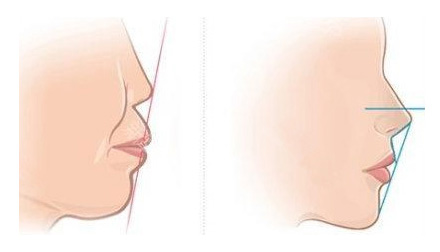

中山松鼠口腔医院美学正畸中心,以每个人的牙颌脸型结构为基础,注重调整牙齿的咬合功能,在解决牙齿排列整体的基础上,重建咬合关系,改善咬合功能。并通过对面部中线的重新梳理,不仅将牙齿排列整齐,还能对容貌改观,让您看起来更漂亮/更英俊。